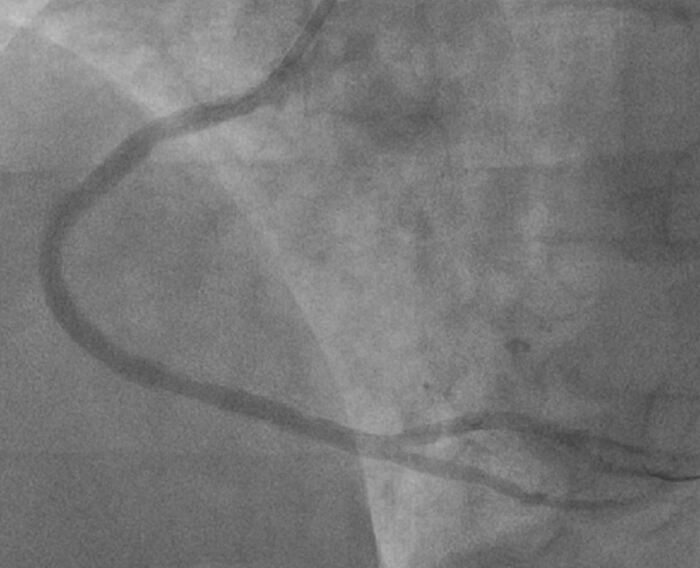

На коронарографии: ствол без стенозов, имеются признаки локальной диссекции (расслоение) передней межжелудочковой артерии в среднем сегменте. Коллатерали к дистальному руслу ПКА.

Правая коронарная артерия (ПКА): стеноз проксимального сегмента до 60%, протяженное поражение среднего сегмента со стенозированием до 70%, протяженное критическое поражение дистального сегмента со стенозированием >90% с замедлением дистального кровотока

Стрелками показаны места сужений правой артерии